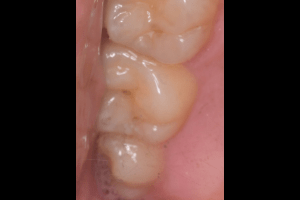

口腔内

- Before

- After

半埋伏の親知らずでした。3糸縫合しました。